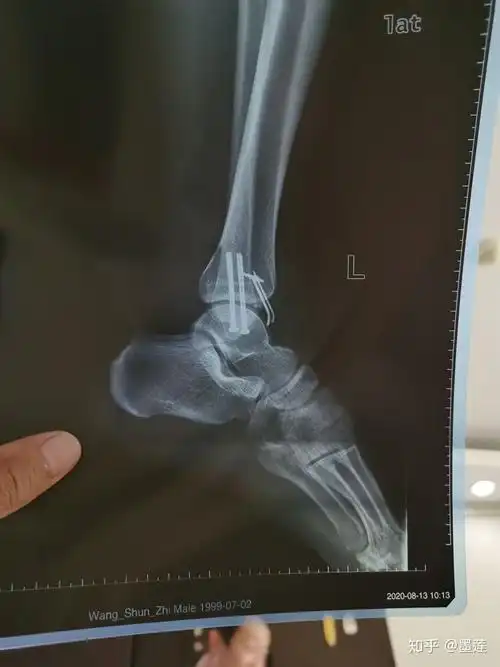

脚踝左腓骨远端骨折月记

左踝关节骨折(denis-web c型)